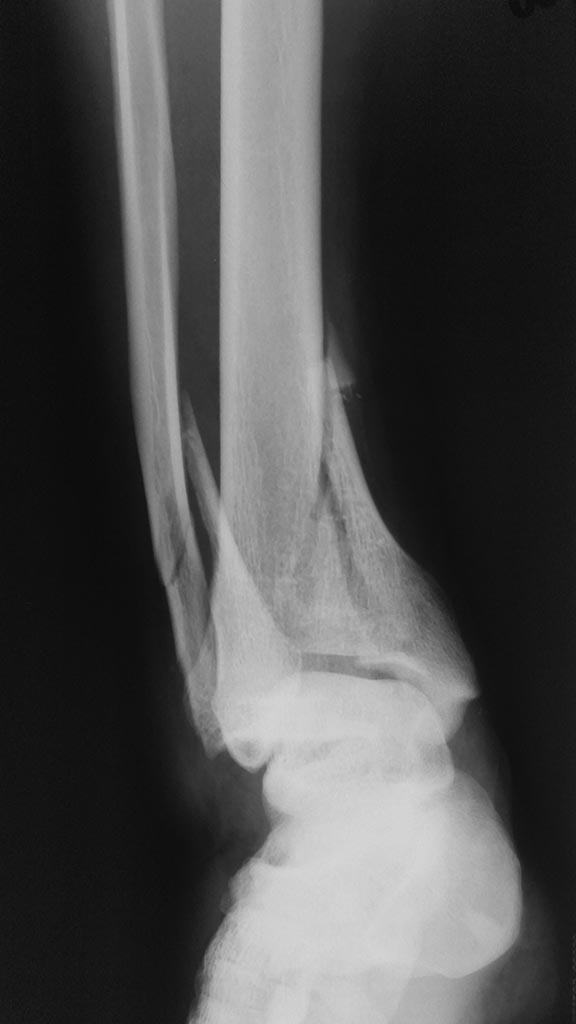

Оскольчатый внутрисуставной перелом костей голени

Пациент 24 года с внутрисуставным оскольчатым переломом дистального метаэпифиза большеберцовой кости, оскольчатым перелом нижней трети малоберцовой кости со смещением отломков.